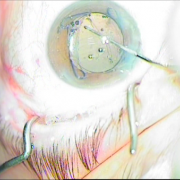

Cat Gionni Ring

Τραυματική διάσπαση ζίνειου ζώνης 5 ωρών

Τραυματική διάσμαση ζήνειου

ζώνης 5 ωρών

Τοποθέτηση ειδικού δαχτυλίου

Φακοθρυψία

Τοποθέτηση αναδιπλούμενου φακού

Τοποθέτηση αναδιπλούμενου

φακού

Τελικό αποτέλεσμα